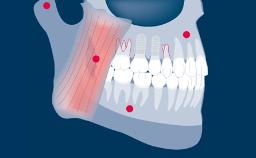

A terapia com implantes provou ser uma modalidade de tratamento bem-sucedida, aplicável em uma ampla gama de indicações clínicas para substituição dentária. Mesmo assim, as complicações ocorrem, e há evidências claras de que as complicações protéticas ocorrem em maior proporção com implantes dentários do que com dentes naturais. Geralmente chamados de “complicações estruturais”, é importante entender porque elas ocorrem e qual a melhor forma de lidar com elas. Este módulo classificará as complicações estruturais do implante associadas às próteses fixas como base para elucidar suas várias causas, melhor prevenção e manejo.